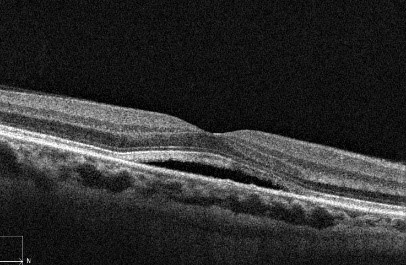

1b.Central serous retinopathy.

1c. Central serous retinopathy